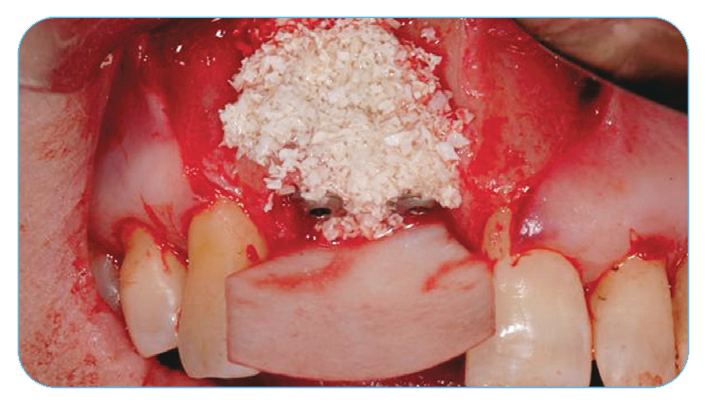

Fig. 11. Grafting with Endobon Xenograft Small Granules covered by an OsseoGuard Resorbable Collagen Membrane.